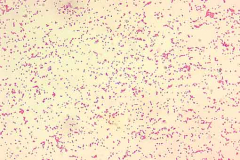

Les salmonelloses sont dues à des salmonelles, des bactéries du genre Salmonella. Certaines salmonelles sont également responsables des fièvres typhoïde et paratyphoïde.

La typhoïde et la parathyphoïde sont dues à des salmonelles (bactéries) particulières, Salmonella typhi et paratyphi.